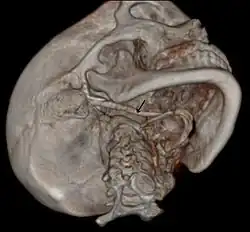

Die Diagnose kann bei klinischem Verdacht mittels Röntgen-Aufnahmen in der Regel als Blickdiagnose im Orthopantomogramm erkennbar, oder mit der Computertomographie gestellt werden. Die Sonographie und die Magnetresonanztomographie sind weniger geeignete Methoden.